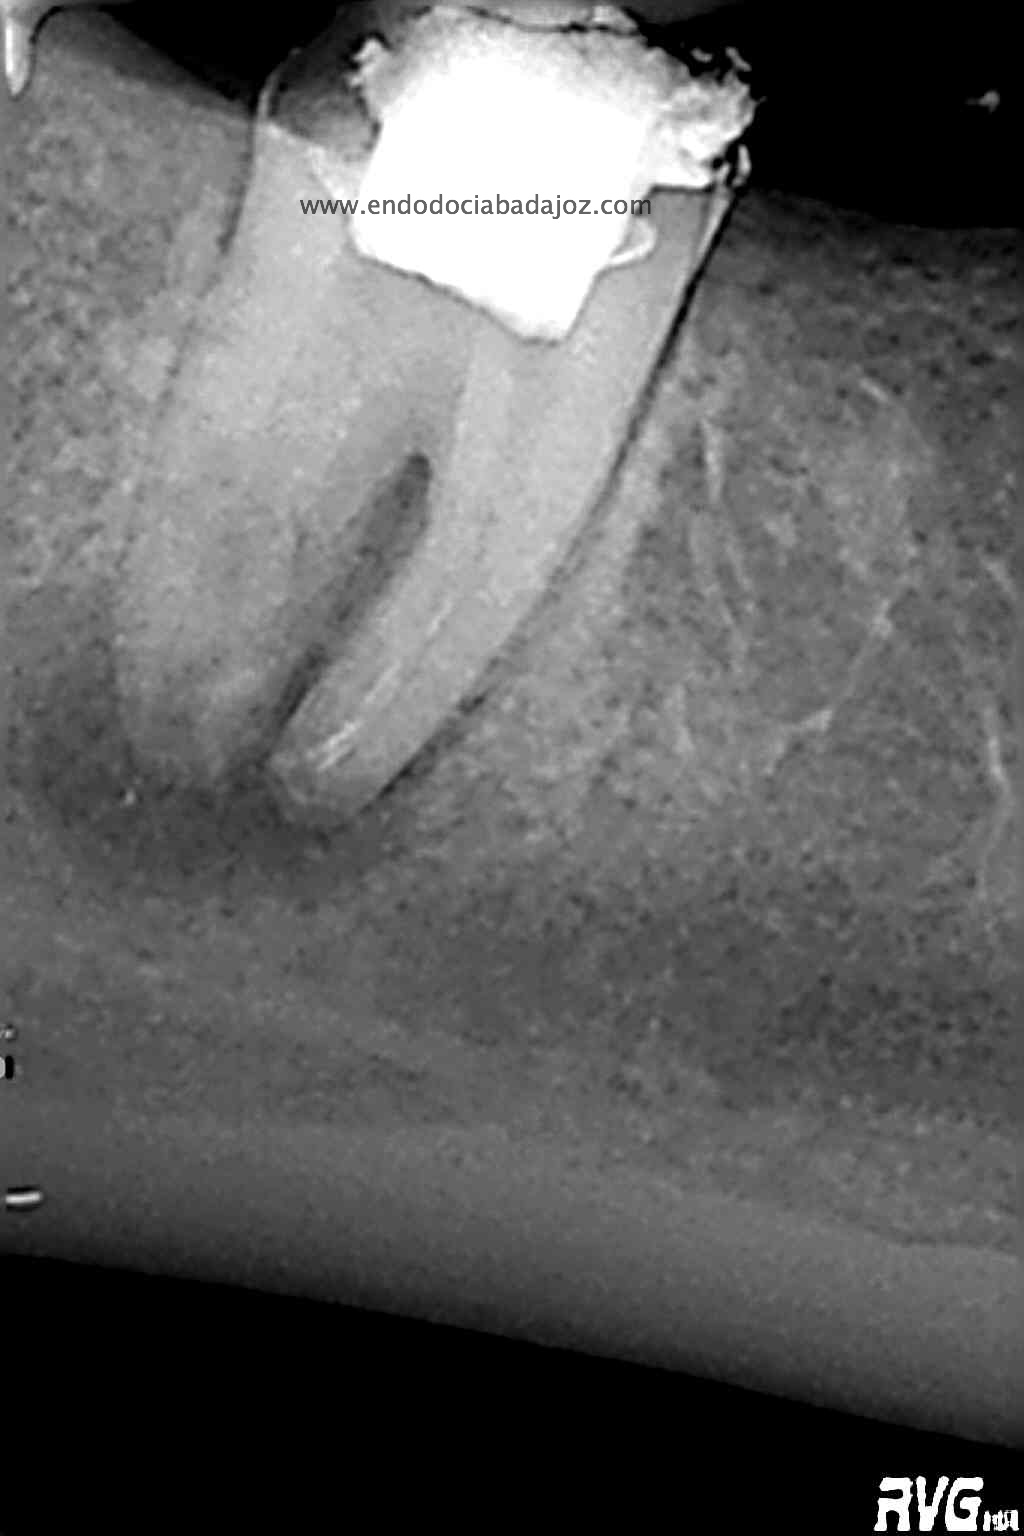

Acude a nuestra clínica una paciente que llamamos a revisión después de realizarle un retratamiento endodóntico de la pieza 4.7 hace unos meses. Si recordamos el día que llegó, no se nos presentaba muy bien el caso, y como otros muchos casos, intentamos retratarlo, pues pensamos que podríamos manejarlo.

Se nos planteaban varios problemas:

Después de plantear el caso, y diseñar unos pasos a seguir, empezamos a realizar el tratamiento.

En un primer paso, retiraríamos el perno y los vástagos del Thermafil, un sistema del que no soy muy partidario, aunque en algunos casos resulta beneficioso.

Este caso lo resolveríamos en varias sesiones, después del manejo de los conductos mesiales, con una preparación biomecánica terminando en una conicidad del 6% y un diámetro apical de 30 en conductos mesiales.

Con ayuda del microscopio, pudimos confirmar que se trataba de una reabsorción interna en el tercio medio y una reabsorción radicular del conducto distal.